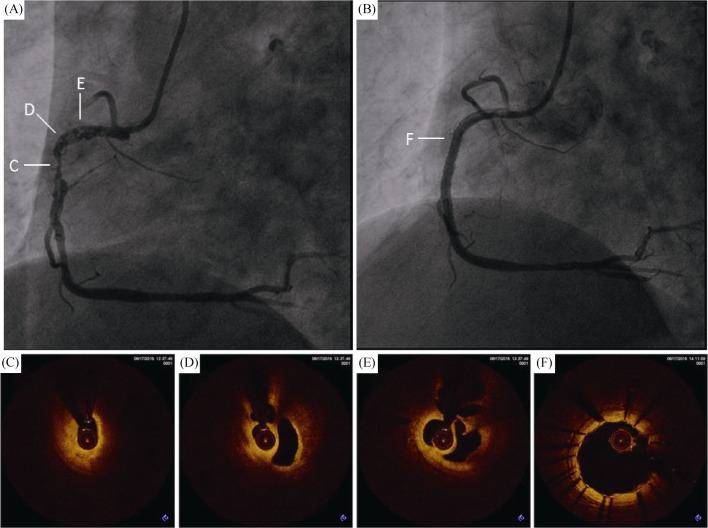

Optimizing woven coronary artery management by optical coherence tomography: three cases report.

https://cdn.ncbi.nlm.nih.gov/pmc/blobs/d8b4/6748902/42aea95d00c2/jgc-16-08-656-g001.jpg